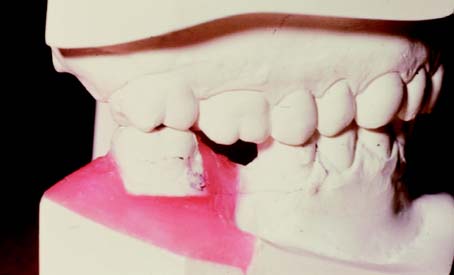

Fig. 6-22 A and B, Use of diagnostic preparations and a dental surveyor in assessing the need for orthodontic treatment before fixed prosthodontics.

Fig. 6-23 A and B, Diagnostic cast sectioning for determination of desired orthodontic tooth movement.